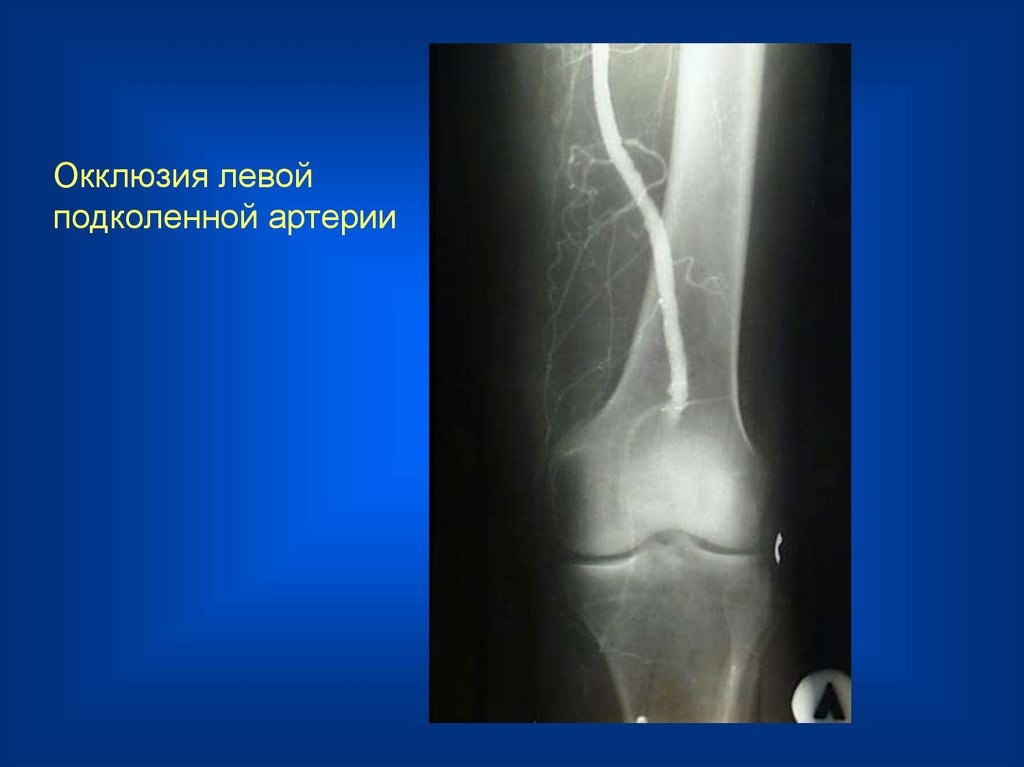

Окклюзия левой

подколенной артерии